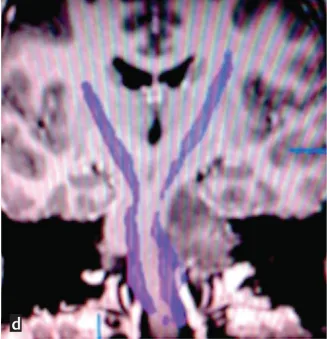

经磁共振成像(MRI)检查发现脑干区域存在巨大肿瘤,累及左侧桥脑、脑桥臂及小脑,肿瘤压迫邻近面神经与听神经导致上述症状。图a、b、c显示脑干巨大占位病变,图d术前扩散张量成像可见肿瘤压迫致皮质脊髓束移位。

鉴于不能排除低级别胶质瘤可能,且存在明显占位效应,医疗团队建议尽早手术明确病理诊断。但由于脑干手术复杂度高,瘫痪风险显著。治疗团队INC德国巴特朗菲教授采用乙状窦后入路,经左侧桥小脑角暴露肿瘤,成功切除50%以上瘤体。因肿瘤累及多数颅神经(CNs V-XI),为避免严重神经功能损伤未行全切。术后除短暂性步态共济失调外,未出现新发神经功能障碍。